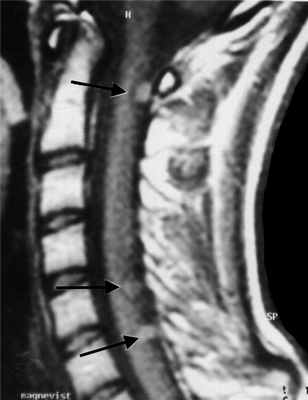

МРТ шейного отдела позвоночника. Нейрофиброматоз тип II. Множественные невриномы (стрелки). Т1-взвешенная МРТ с контрастированием.

Невриномы (шванномы) и нейрофибромы составляют примерно половину опухолей этой локализации и 35% от всех спинальных опухолей. Гистологически невриномы происходят из шванновских клеток оболочек нерва (леммоцитов), прилегающих к заднему корешку. Обычно диагностируются они в возрасте 20 – 50 лет, у мужчин проявляются несколько в более молодом возрасте, чем у женщин. Они почти всегда одиночные, инкапсулированные, располагаются в любом отделе, но чуть чаще в поясничном или верхнем шейном. Множественные невриномы встречаются исключительно редко при нейрофиброматозе типа II. Нейрофибромы состоят из шванновских клеток и фибробластов, некоторые окружают задний корешок. Они почти всегда множественные и связаны с нейрофиброматозом типа I (болезнь Реклингхаузена). От 2 до 12% нейрофибром перерождаются злокачественно, превращаясь в нейрофибросаркомы. Несмотря на различие в гистологии характер роста опухолей одинаковый. Около 15% из них распространяются в экстрадуральное пространство через одно или несколько межпозвоночных отверстий, приобретая вид “песочных часов”. Такой тип роста особенно типичен для шейной локализации. На рентгенограммах рост по типу «песочных часов» может быть выявлен по расширению межпозвоночного ответстия и эрозии корня дуги. Клинические проявления неврином и нейрофибром состоят в радикулопатическом и миелопатическом синдромах.

На МРТ Т1-взвешенного типа и невриномы, и нейрофибромы изо- или слегка гипоинтенсивны по отношению к спинному мозгу. Однако, встречаются случаи и повышенного сигнала за счет сокращения Т1 мукополисахаридами, связанными с водой. Протонная плотность при МРТ повышена, а на Т2-взвешенных МРТ они чаще неоднородные, могут быть очень яркие участки, где имеется высокое содержание воды, и сравнительно низкого сигнала, особенно в центре. Обе опухоли хорошо контрастируются при МРТ. По форме невриномы округлые, границы ровные, четкие. Нейрофибромы вытянуты вдоль корешка, что лучше видно на корональных МРТ. Размеры могут быть самыми различными.